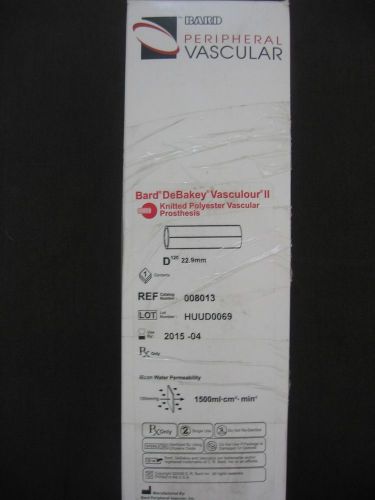

Vascular graft Bard Debakey AORTIC implant knitted polyester prosthesis